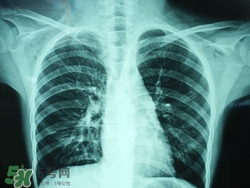

肺炎是常見的呼吸道感染疾病,這病也確實(shí)麻煩,如果處理不當(dāng)可能危及生命哦,那么肺炎會(huì)不會(huì)傳染呢?吃什么好的快呢?下面我們來介紹下吧!